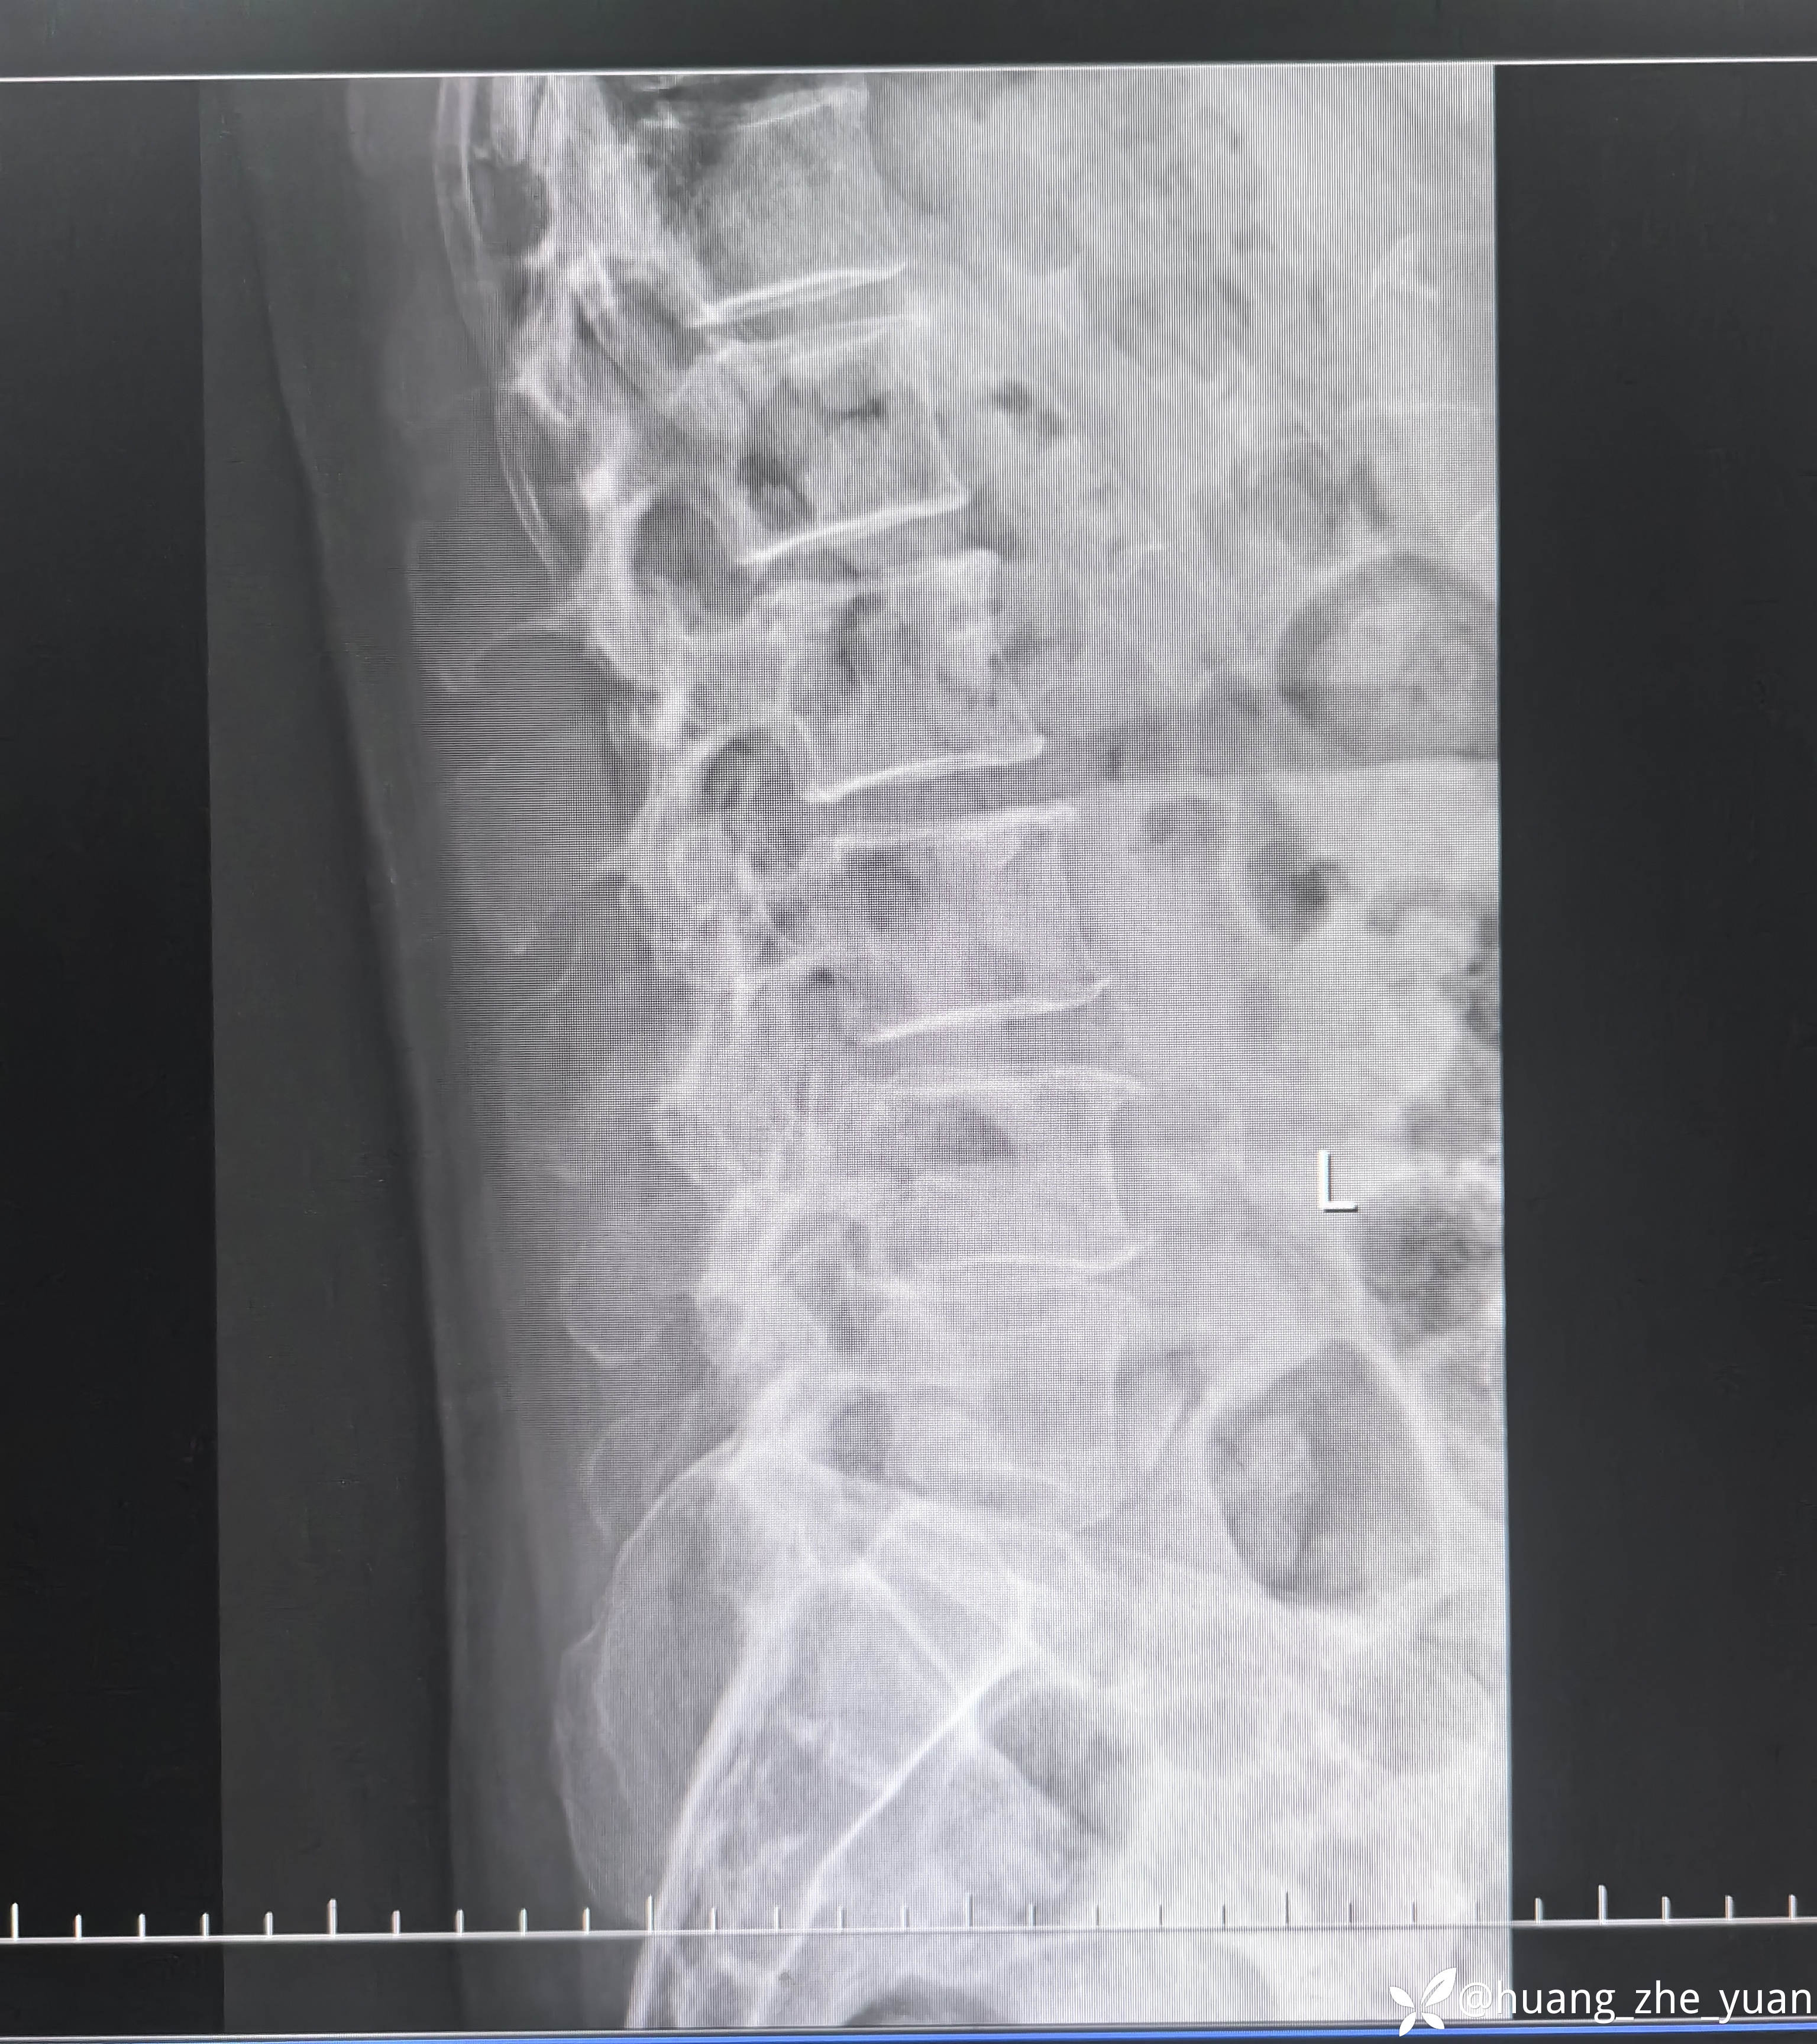

70岁女性,反复右下肢放射痛八个月。合并症:糖尿病,胰岛素泵控制。